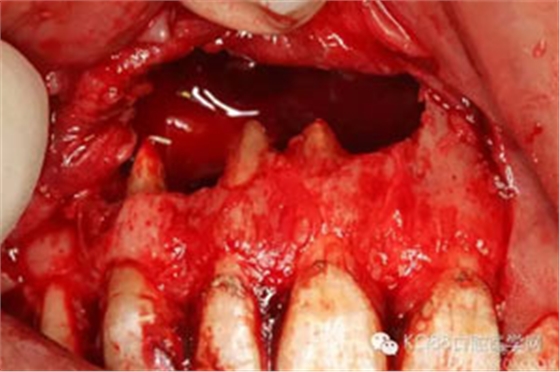

圖6.即將游離的囊腫上皮組織。

圖7.囊壁被完整摘除后遺留的巨大骨腔,11根尖牙膠尖依稀可見。